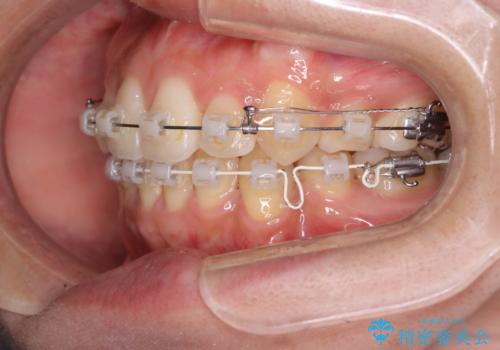

- クリア装置

- 八重歯を主訴に来院されました。4番の歯を4本抜歯し、八重歯を並べる計画をたてました。

抜歯をし、スペースを確保したことにより八重歯をきれいに並べることが出来ました。